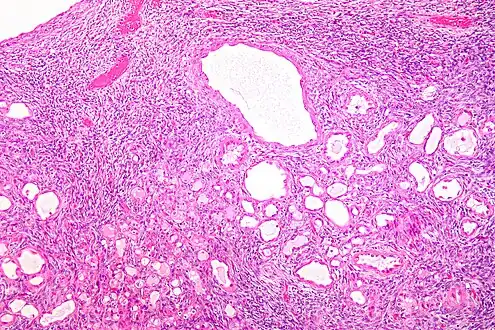

| Micrograph of a cystic nephroma (left of image). Normal kidney is seen on the right. H&E stain. | |

Cystic nephroma: Microscopic appearance. -

Micrograph of a cystic nephroma. H&E stain.

The characteristics of cystic nephromas are:

- Cysts lined by a simple epithelium with a hobnail morphology, i.e. the nuclei of the cyst lining epithelium bulges into the lumen of the cysts,

- Ovarian-like stroma that has a:

- Spindle cell morphology, and has a

- Basophilic cytoplasm.